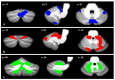

The aim of this study was to compare the patterns of cerebellar alterations associated with bipolar disease with those induced by the presence of cerebellar neurodegenerative pathologies to clarify the potential cerebellar contribution to bipolar affective disturbance. Twenty-nine patients affected by bipolar disorder, 32 subjects affected by cerebellar neurodegenerative pathologies, and 37 age-matched healthy subjects underwent a 3T MRI protocol. A voxel-based morphometry analysis was used to show similarities and differences in cerebellar grey matter (GM) loss between the groups. We found a pattern of GM cerebellar alterations in both bipolar and cerebellar groups that involved the anterior and posterior cerebellar regions (p = 0.05). The direct comparison between bipolar and cerebellar patients demonstrated a significant difference in GM loss in cerebellar neurodegenerative patients in the bilateral anterior and posterior motor cerebellar regions, such as lobules I-IV, V, VI, VIIIa, VIIIb, IX, VIIb and vermis VI, while a pattern of overlapping GM loss was evident in right lobule V, right crus I and bilateral crus II. Our findings showed, for the first time, common and different alteration patterns of specific cerebellar lobules in bipolar and neurodegenerative cerebellar patients, which allowed us to hypothesize a cerebellar role in the cognitive and mood dysregulation symptoms that characterize bipolar disorder.